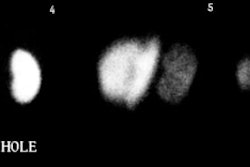

On scintigraphy there is poor to no renal perfusion and poor parenchymal tracer accumulation of tubular agents (little to no renogram). The kidney may appear as a photopenic region.